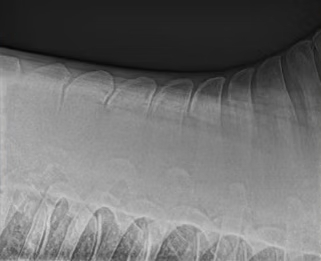

Vortrag „Kissing Spines“ von Dr. Nils Adolphsen

Bei der Fortbildungsveranstaltung in unserer Klinik mit derbymed-Livisto im November 2019 hat Dr. Nils Adolphsen zum Thema „Kissing Spines – Wo stehen wir heute unter besonderer Berücksichtigung der OP-Techniken“ einen informativen Vortrag gehalten.

Wie immer gerne zum Nachlesen für alle Interessierte: Vortrag